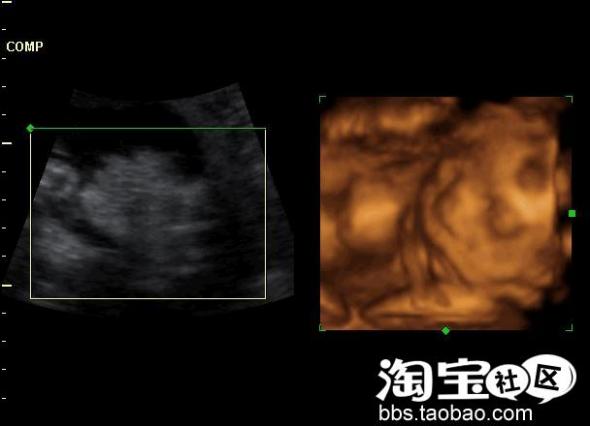

我相信了,结果我的防备心理完全解除,电脑想上就上,这段时间持续了8个月。这期间,有很多人叫我不要用电脑,说对宝宝不好,我一直是半信半疑,也开始有了担心,所以我在6个月的时候做了四维彩超

我见到了宝宝在我肚子里的样子,看见宝宝蛮健康的,没有检查出畸形, 我忐忑的心放下了不少。可在临产前两个月,不安和紧张的心理又出现了,想想即使是四维彩超,尽管能发现绝大部分胎儿畸形,但受胎儿胎龄,姿势,羊水,活动等诸多因素影响以致部分器官与部分超声无法显示或显示不清,因此,诊断胎儿畸形符合率不可能100%。我想我会不会得了产前忧郁症呢!呵呵!!即使我现在控制上网时间、穿好防辐射YY会不会也晚了呢?